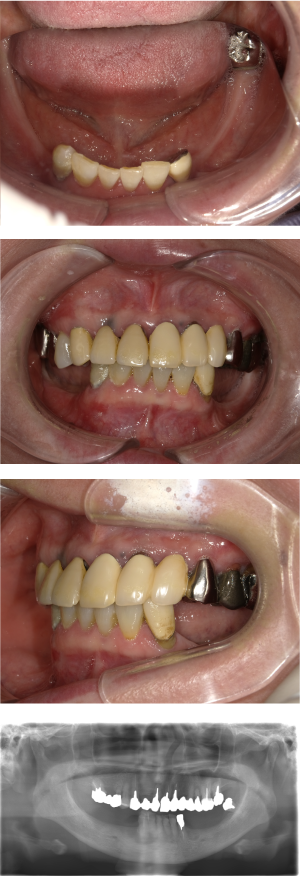

インプラント治療(左上5ソケット・GBR 右上2左上13GBR)

| 年代・性別 | 50代・男性 |

| 主訴 | 入れ歯だと咬めなくてつらい。 |

| 部位 | 上顎②1①2③4⑤Br |

| 治療期間 | 約9ヶ月 |

| 費用 | ¥1,794,100(税込) |

| 副作用・リスク |

|